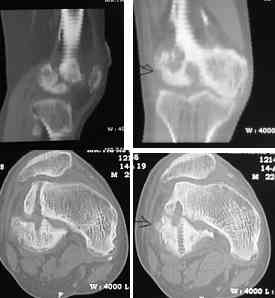

This 20 year old patient sustained a fracture in the lower end of the femur, one and a half years ago, with a compound wound over the fracture area.

Notes at that time mention a compound fracture dislocation, with a loss of part of the lateral condyle. This was treated by debridement, and external fixation. After two weeks, the lateral condyle (coronal fracture) was fixed by a screw and k wire in an AP direction.

At present, he has a valgus deformity of the knee, with 0-45 degrees of movt. The knee is stable to examination, could not be corrected to neutral from the existing valgus, and despite the deformity he is walking on it, albeit with pain and some difficulty.